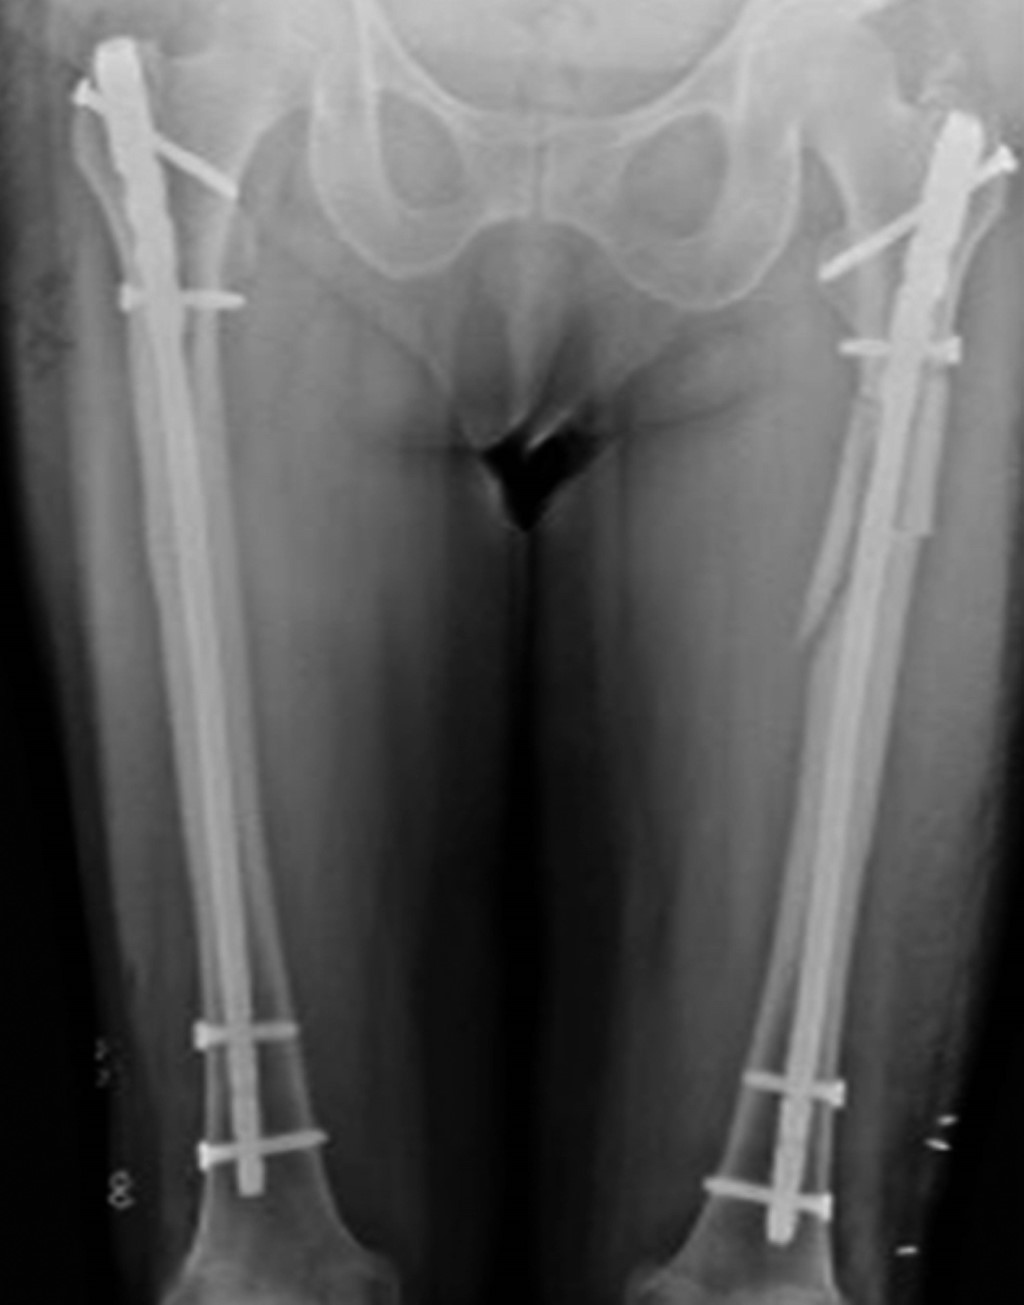

An 83-year-old female with a 10-year history of bisphosphonate treatment for osteoporosis (alendronic acid, 70 mg presentation), came to the orthopedic consult after feeling leg pain. Normal movement, with limitation and instability, while standing up. An X-ray and CT scan of the pelvis were obtained. Figure 1 shows the thickening of the bone cortex, with the presence of atypical incomplete bilateral fractures in the subtrochanteric femur. After a complete assessment, the patient underwent surgical treatment with intramedullary nailing (Figure 2), and thromboprophylaxis with Apixaban 2.5 mg every 12 hours for 28 days was indicated.

Figure 1